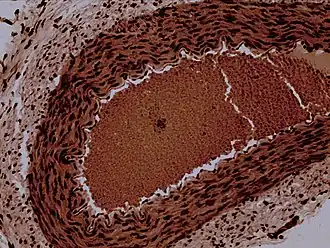

Rabbit arteriole at 100X

An arteriole is a small-diameter blood vessel in the microcirculation that extends and branches out from an artery and leads to capillaries.[1]

Arterioles have muscular walls (usually only one to two layers of smooth muscle cells) and are the primary site of vascular resistance. The greatest change in blood pressure and velocity of blood flow occurs at the transition of arterioles to capillaries. This function is extremely important because it prevents the thin, one-layer capillaries from exploding upon pressure. The arterioles achieve this decrease in pressure, as they are the site with the highest resistance (a large contributor to total peripheral resistance) which translates to a large decrease in the pressure.[2]